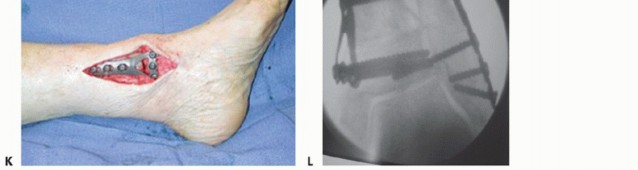

TECH FIG 1 • Medial closing wedge supramalleolar osteotomy. A. Using a preoperative radiograph, the center of rotation of angulation (CORA) is located at the intersection of two lines that represent the mechanical axes of the proximal and distal segments. B. Under fluoroscopy, a Kirschner wire is inserted to the tibia perpendicular to the mechanical axis and a second Kirschner wire is inserted parallel to the ankle joint line intersecting the first wire, ideally at the apex of the deformity. C,D. Guide pin wires used to perform a closing medial wedge osteotomy. Pin A has been inserted to the tibia perpendicular to the mechanical axis and pin B has been inserted parallel to the ankle joint line, intersecting pin A at the apex of the deformity. E. The cut wedge. The pins have been used as a guide for the tibial cuts, whereas the size of the wedge has been determined during the preoperative planning. (continued)

- TECH FIG 1 • (continued) F. Fluoroscopic view of the resected wedge. G. Fluoroscopic view of the closed osteotomy. H,I. Fluoroscopic AP and lateral views of the provisionally fixed osteotomy with Kirschner wires. J. Photo of the applied periarticular plate. Note the excellent fit on the distal tibia. K. The applied periarticular plate after completion of fixation with three screws in the distal segment. L. Fluoroscopic view of the osteotomy after completion of fixation.

Several dedicated low-profile periarticular plating systems for the distal tibia are marketed, both locking and nonlocking. The majority of these plates were designed for the contours of the physiologic tibia. With a wedge resection, the fit is typically acceptable but may not be perfect. Locking plates may provide optimal stability, but if the osteotomy is not fully closed, these may in fact delay or even hinder healing.

Nonlocking plates, in our opinion, allow for a small amount of settling at the osteotomy with weight bearing, potentially facilitating healing. (If additional stability is required, then cannulated or solid screws may be used from the tip of the medial malleolus across the osteotomy. Alternatively, a second plate may be added anteriorly on the tibia to provide rotational control to the tibia; however, this requires greater soft tissue dissection.)

We do not routinely apply fixation to the fibula, but if additional stability is required, then we apply a low-profile fibular plate.

Final fluoroscopic images in the AP and lateral planes confirm proper alignment, apposition of the osteotomy, and position of hardware. -